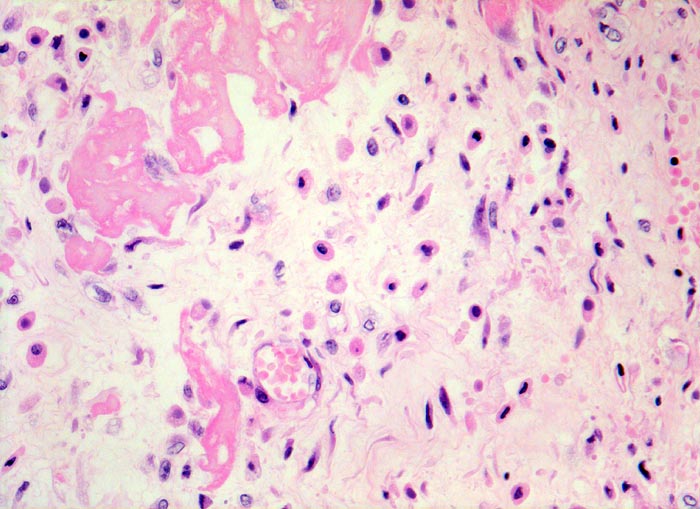

fibrinöse Perikarditis

Lockeres ödematöses Granulationsgewebe mit kapillären Gefässen, Histiozyten (Gewebsmakrophagen) und Fibroblasten organisieren die Fibrinauflagerungen.

Patientin verstorben in Urämie.

Histologie

320